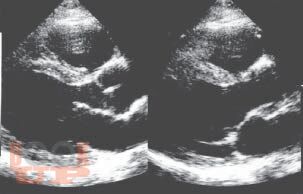

Книга посвящена одному из важнейших разделов детской кардиологии - врожденным порокам сердца. В общей части рассмотрены особенности нормального кровообращения у плода и новорожденного, а также его изменения при врожденной патологии сердца; кроме того, читатель знакомится со специальной терминологией. В разделе частной патологии подробно представлены все основные пороки, встречающиеся в практике детских врачей, алгоритмы их диагностики, современные возможности терапевтического и хирургического лечения; изложены вопросы послеоперационного наблюдения за пациентами. Издание содержит более 140 рисунков и схем, иллюстрирующих ключевые расстройства гемодинамики, методы исследования сердца и наиболее распространенные операции.

Изображения 84